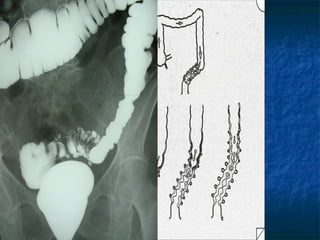

Pseudo-diverticolo Erniazione della mucosa, della sottomucosa e della muscolaris mucosa attraverso la tonaca muscolare circolare nel grasso pericolico Dimensioni: 5-10 mm (fino a 20 mm) DEFINIZIONE Mucosa Sottomucosa Muscolare circolare Muscolare longitudinale

PATOGENESI Legge di Laplace  P = k  T r Tenia antimesenterica Tenia mesenterica Muscolatura circolare Vasi retti

Pseudo-diverticolo Erniazione dellamucosa, della sottomucosa e della muscolaris mucosa attraverso la tonaca muscolare circolare nel grasso pericolico Dimensioni: 5-10 mm (fino a 20 mm) DEFINIZIONE Mucosa Sottomucosa Muscolare circolare Muscolare longitudinale

PATOGENESI Legge diLaplace P = k T r Tenia antimesenterica Tenia mesenterica Muscolatura circolare Vasi retti